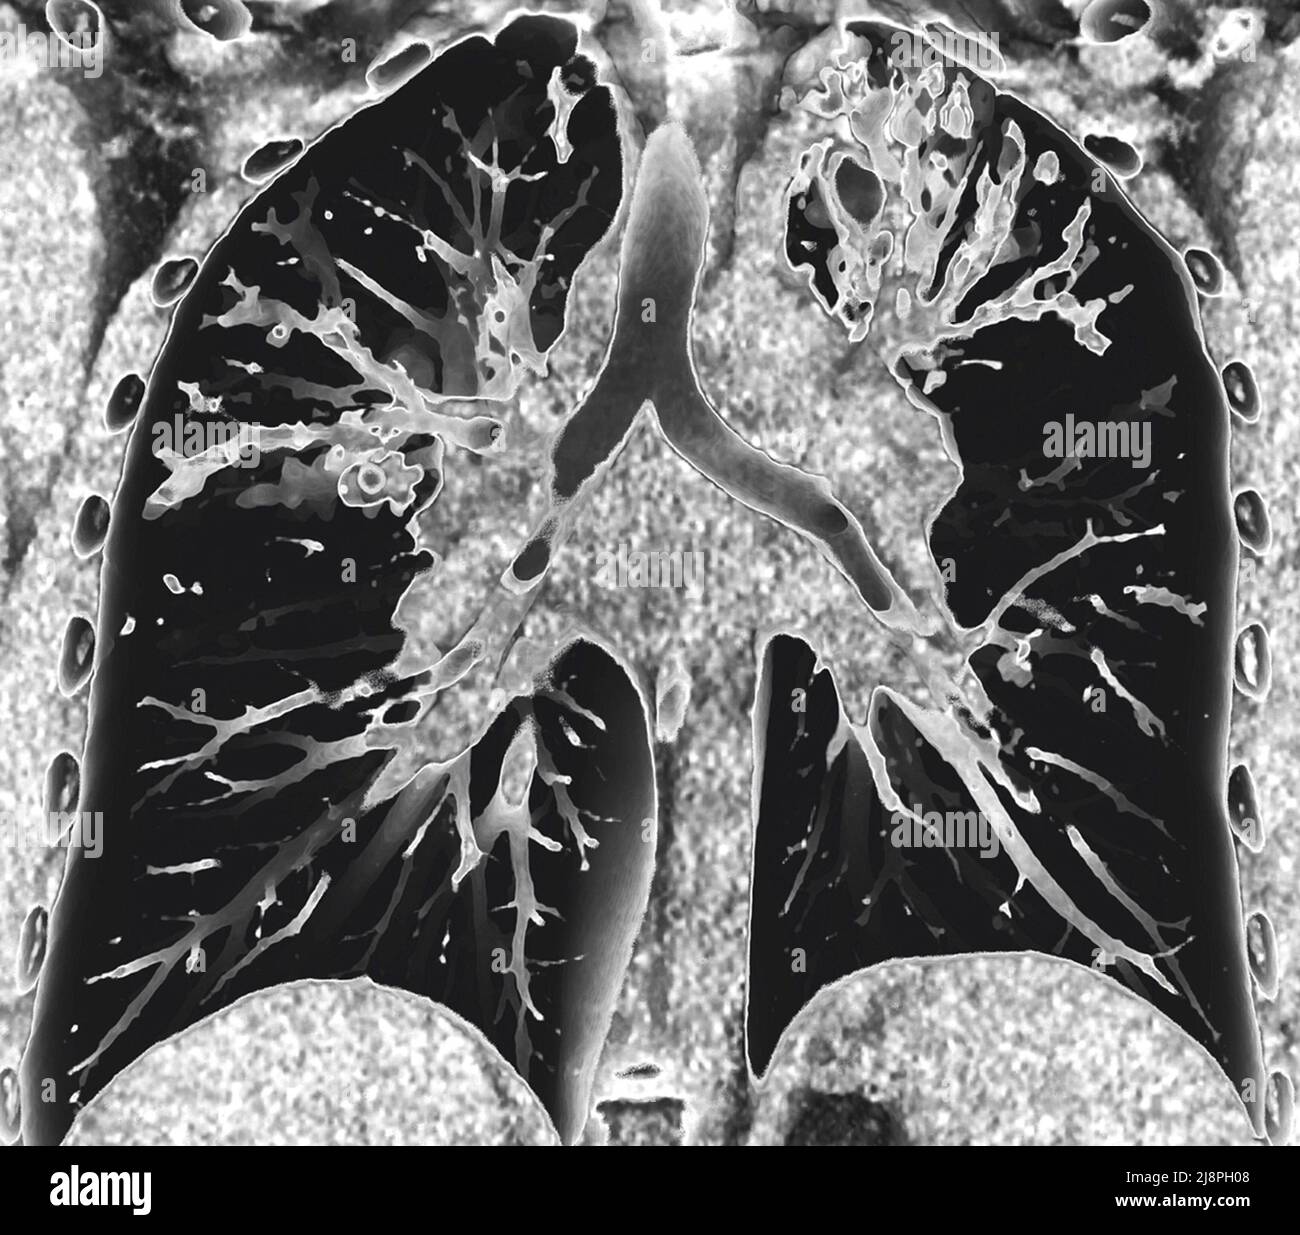

From www.sciencephoto.com

Bronchiectasis, CT scan Stock Image C036/6384 Science Photo Library Bronchiectasis On Spirometry spirometry is one of the more common tests of lung function. Forced spirometry manoeuvres measure how hard and fast a. — the present study was undertaken with an aim to assess the clinical profile and functional impairment using. — international guidelines recommend simple spirometry for bronchiectasis patients. — the rationale for surgical treatment of bronchiectasis is. Bronchiectasis On Spirometry.